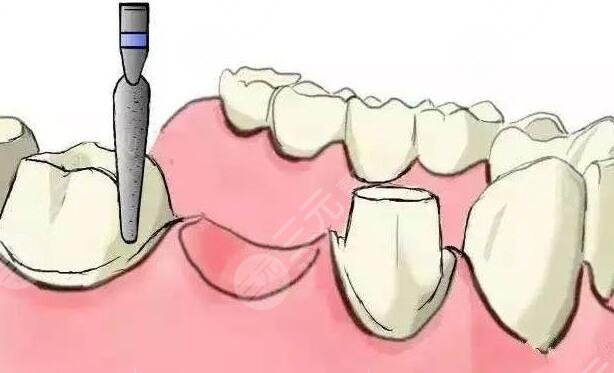

韩国登腾种植牙多少钱一颗2023?牙齿种植技术比较受欢迎,而且也是比较常见的修复牙齿的一种方式,主要是通过植入种植体然后再做烤瓷冠修复,这样就完成了种植牙种植牙体系分为很多韩国种植牙就比较受欢迎。韩国登腾种植牙是使用率比较高的,而且范围也比较广泛,但是关于价格的问题很多人不清楚。那么:韩国登腾种植牙多少钱一颗?其实在选择韩国登腾种植牙体系之前,关于价格的问题也是应该了解的话题。

韩国登腾种植牙,采用的是四级纯钛的材质,植体表面采用的是S.L.A处理技术。登腾种植牙,表面也能够有效提高初期的稳定性,而且能够跟牙槽骨紧密的结合在一起,缩短了牙齿种植的时间。韩国登腾种植牙主要是为黄皮肤的人群进行设计,能够带来更加坚固稳定的效果。